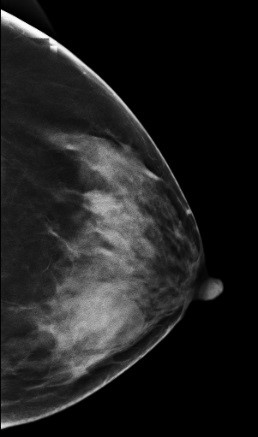

DBT图像:

影像描述: 常规2D图像MLO位左乳腺内见多个小结节影,下象限似见一团块影,边界模糊,CC位上并没有发现异常团块影,在V-Perview图像MLO位下象限见一类圆形团块影,部分边界尚清,但CC位上并没发现明显异常团块影,DBT断层图像在MLO和CC位上左乳内下象限清晰可见类圆形致密影,其边缘光滑锐利。 影像诊断: 左侧乳腺多发良性结节,BI-RADS 3。 病例点评: 最后病理证实纤维腺瘤,类似这样病例DBT可以给我们提供更多诊断信息有助于明确病变性质。